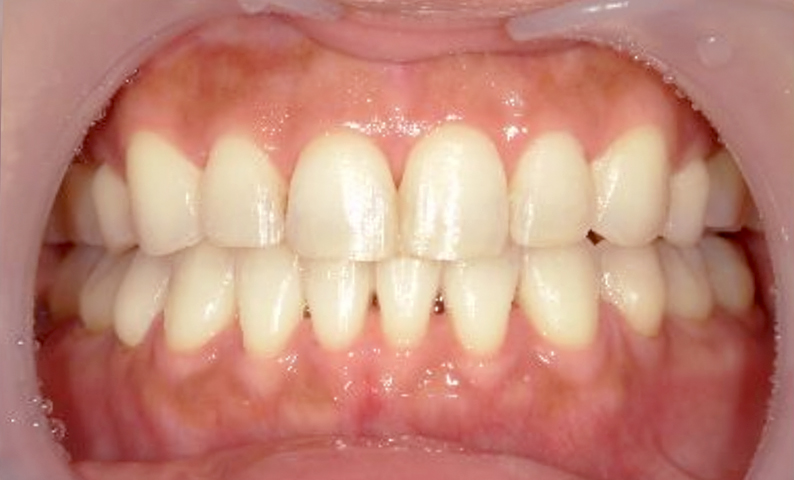

症例_003 下顎だけの部分矯正

治療期間:10ヶ月金額:24万円+税女性前歯のガタガタ下の前歯だけ上顎は補綴治療中

| Before | After |